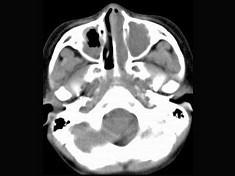

男,7岁,无意发现鼻腔肿物,无明显症状,CT如图所示,最可能诊断为 ( )

• A.鼻炎鼻息肉

答案: A